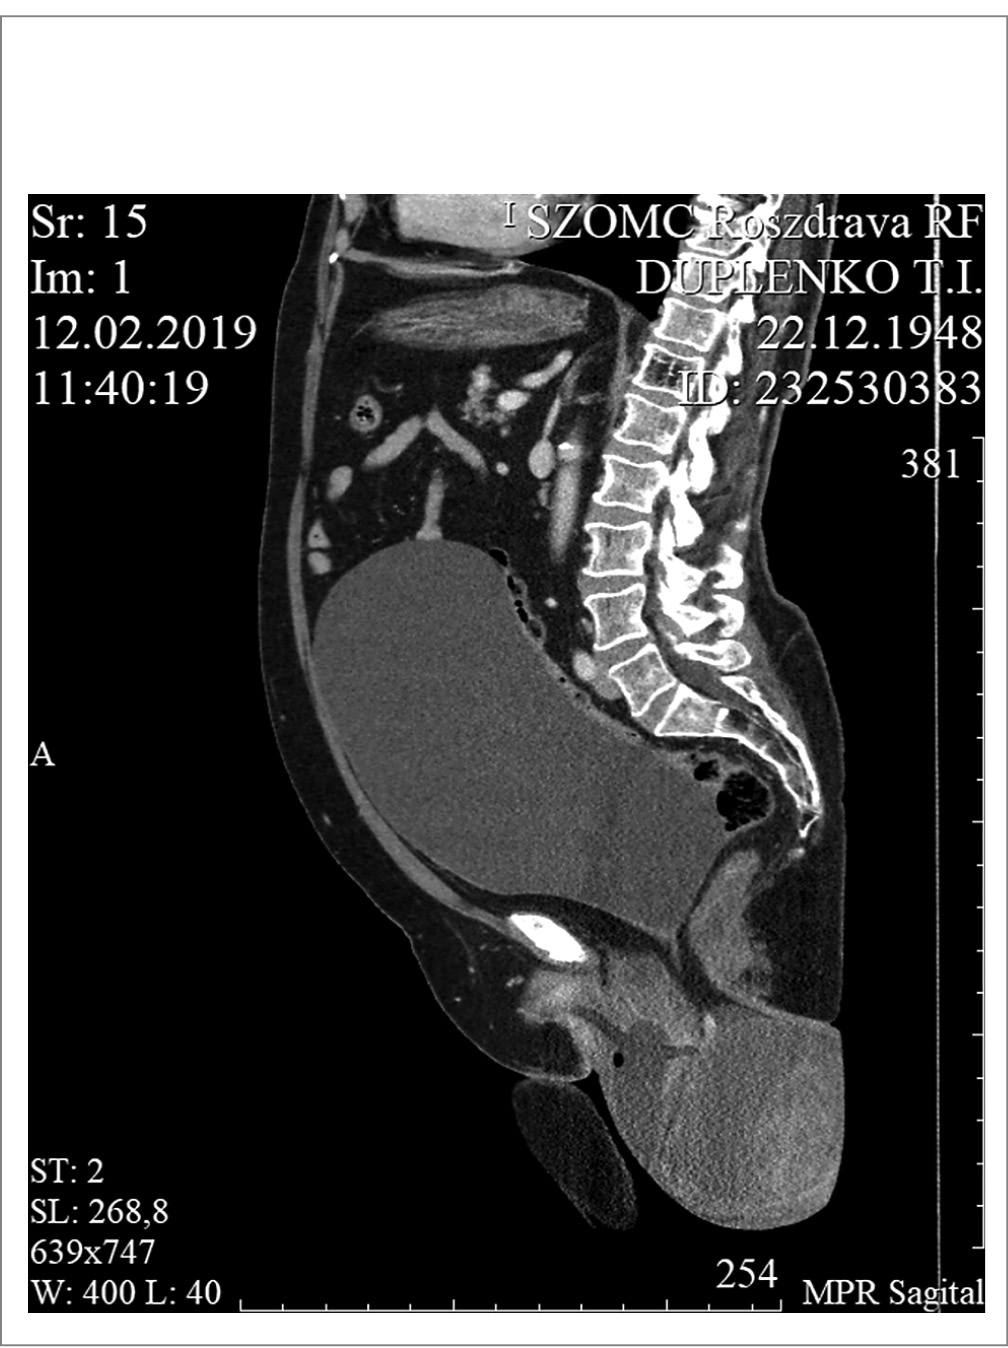

Результаты спиральной компьютерной томографии (КТ) ОМТ с внутривенным болюсным контрастированием (Toshiba Aquilion 64, США). КТ-признаки пролапса тазового дна. Патологическое образование матки. Кистовидное образование правого яичника 12,0×16,0×25,0 см. Левый яичник не визуализируется. Матка и мочевой пузырь расположены ниже уровня тазового дна, на уровне верхних отделов бедер (рис. 1).

Рис. 1. Компьютерная томография органов малого таза.

Fig. 1. Computed tomography of the pelvic organs.

Заключение. КТ-признаки пролапса тазового дна. Патологическое образование матки. Кистовидное образование правого яичника (рис. 2, 3). Учитывая полученные при дообследовании пациентки данные, выставлен диагноз. Основной: новообразование правого яичника? ТхNxMx. Миома матки, нарушение питания узла? Фоновый: стрессовое недержание мочи в сочетании с опущением ОМТ. Полное выпадение матки и влагалища.